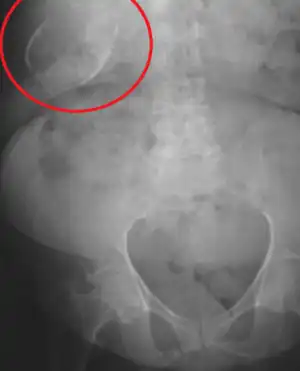

| Porcelain gallbladder on X-ray | |

Porcelain gallbladder is a calcification of the gallbladder believed to be brought on by excessive gallstones, although the exact cause is not clear. As with gallstone disease in general, this condition occurs predominantly in overweight female patients of middle age. It is a morphological variant of chronic cholecystitis. Inflammatory scarring of the wall, combined with dystrophic calcification within the wall transforms the gallbladder into a porcelain-like vessel. Removal of the gallbladder (cholecystectomy) is the recommended treatment.

Abdominal radiography (X-ray), abdominal ultrasound or CT scan.